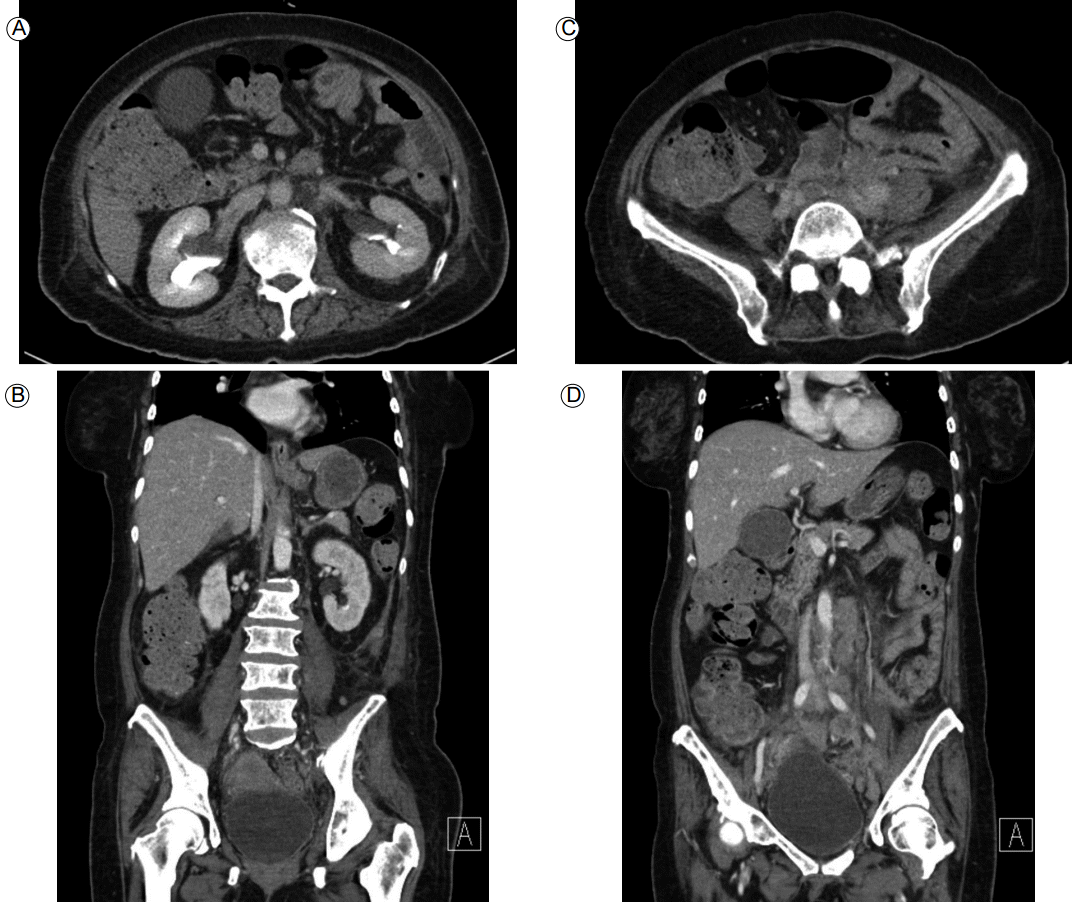

Figure 6.

Abdominal computed tomography showed diffuse infiltrating soft tissue with interval improvement in the retroperitoneal space (A, B) and in the pelvic cavity (C, D).